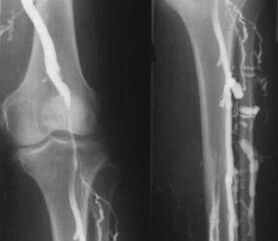

The most common instrumental diagnostic method is the use of ultrasound examination of the venous vessels of the legs.This technique allows you to visualize the vascular system and identify the degree of advancement of the pathological process.

- Phlebography.

- Photoplethysmography.

The use of venous occlusion plethysmography makes it possible to determine the volume of blood in the veins of the lower extremities.